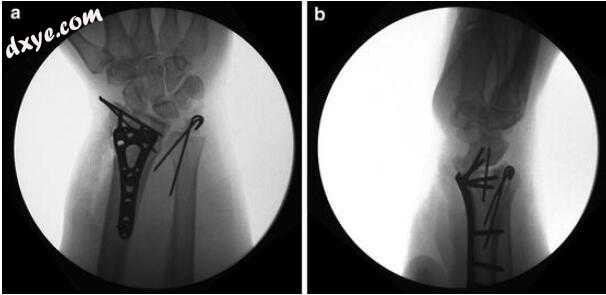

2.jpg

图3.2术中PA(a)和侧(b)X线片。 进行了掌侧锁定板固定,在桡骨茎突中添加了补充的克氏针,因为只有一个螺钉可以放置在茎突片段中。 尺骨茎突用克氏针固定,因为DRUJ不稳定直至进行。 注意到舟月距离变宽; 然而,与旧的X光片相比,证实这是一种慢性韧带损伤,而不是急性撕裂